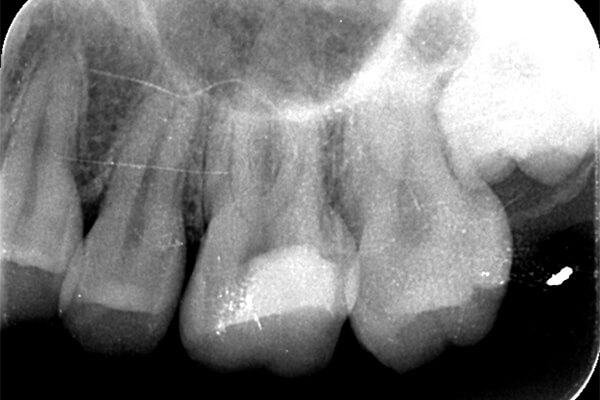

こちらは虫歯で神経を取らないといけなくなりましたが、何度治療しても痛みが消えないと言うことで当院にいらっしゃいました。度重なる治療で歯の神経のあった場所がかなりひろげられており、また根の先端も破壊されている状態でした。ですので、痛みが消えないのです。

肉眼では根の先端は見ることができませんがマイクロスコープでは見ることができます。根の先端をこれ以上破壊しないように清掃して歯の神経があった場所にお薬を詰めることができました。根の治療後、かぶせ物までして半年たっても痛みがありません。

レントゲンを見ていただいて、歯の先までしっかり白いお薬が入っているのがわかります。